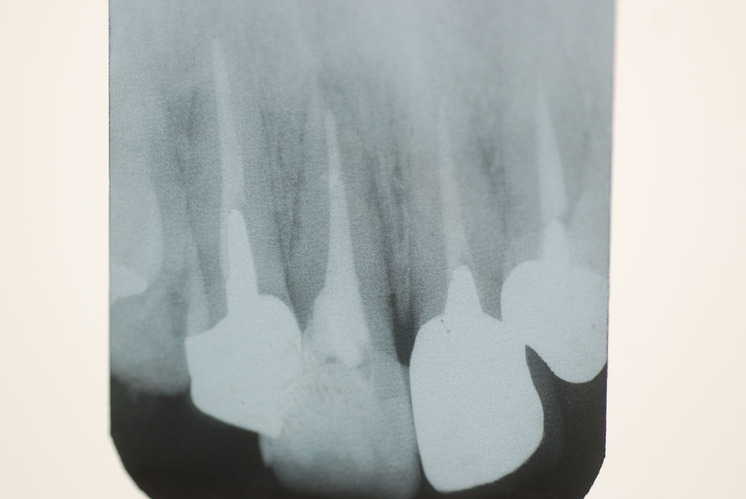

歯周病の疑いで東京のかなり遠方の方が来院されました。

驚くべきことですが、定期検診は受けていたそうです。しかしながら歯周病の指摘は受けたことがないそうです。

何故か?定期検診が虫歯のチェックのみになり、又肝心の歯周病の検査や歯周病の部分の予防や治療のためのブラシの使い方などを学んだ事がないのです。